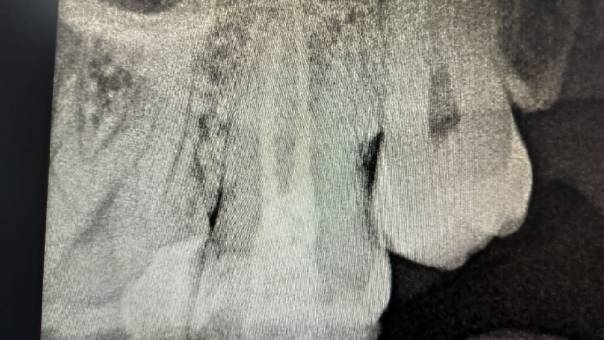

Clinical and Radiographic Findings:

On examination, mild tenderness was noted when

tapping on tooth 27. A radiographic evaluation

revealed that the distal canal of the tooth had been

inadequately treated and left unfilled. This had led

to a localized periapical infection.

Locating the distal canal

After Obturation

Unfilled distal canal pre-operation